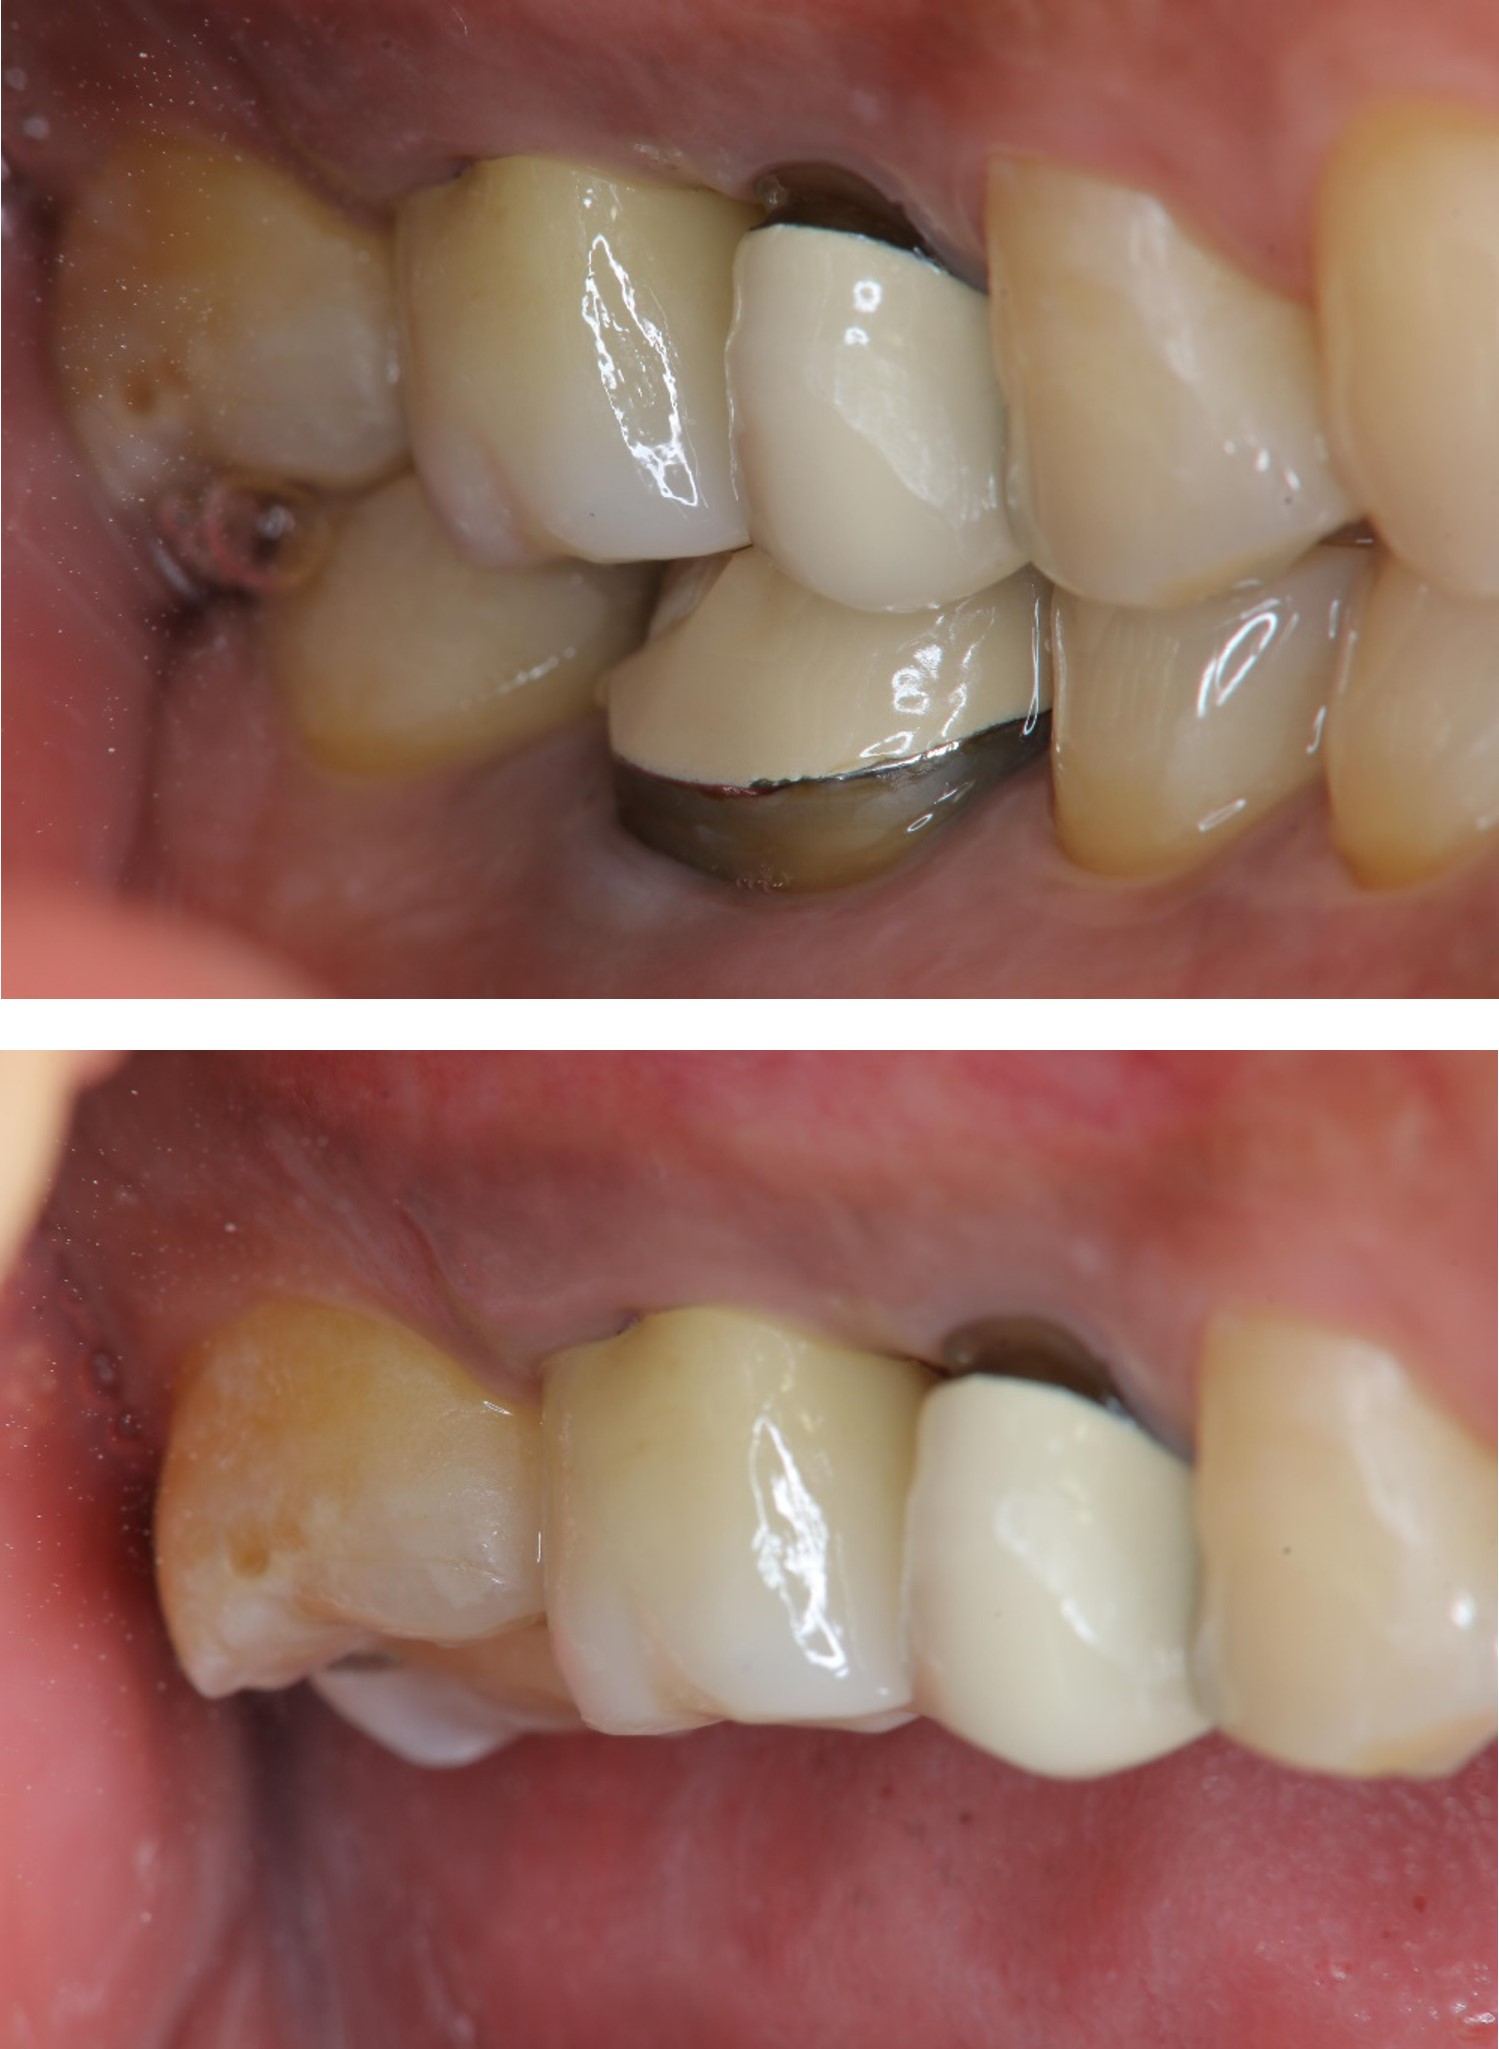

膺復前評估牙齦、牙齒狀態

治療後,咬合良好

治療後,密合度良好

術前、術後比較